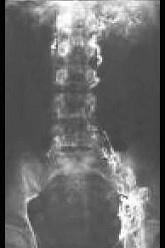

问题 乳糜尿最常见的原因为 ( )

选项 A、肿瘤 B、梗阻 C、结石 D、丝虫病 E、结核

答案 D